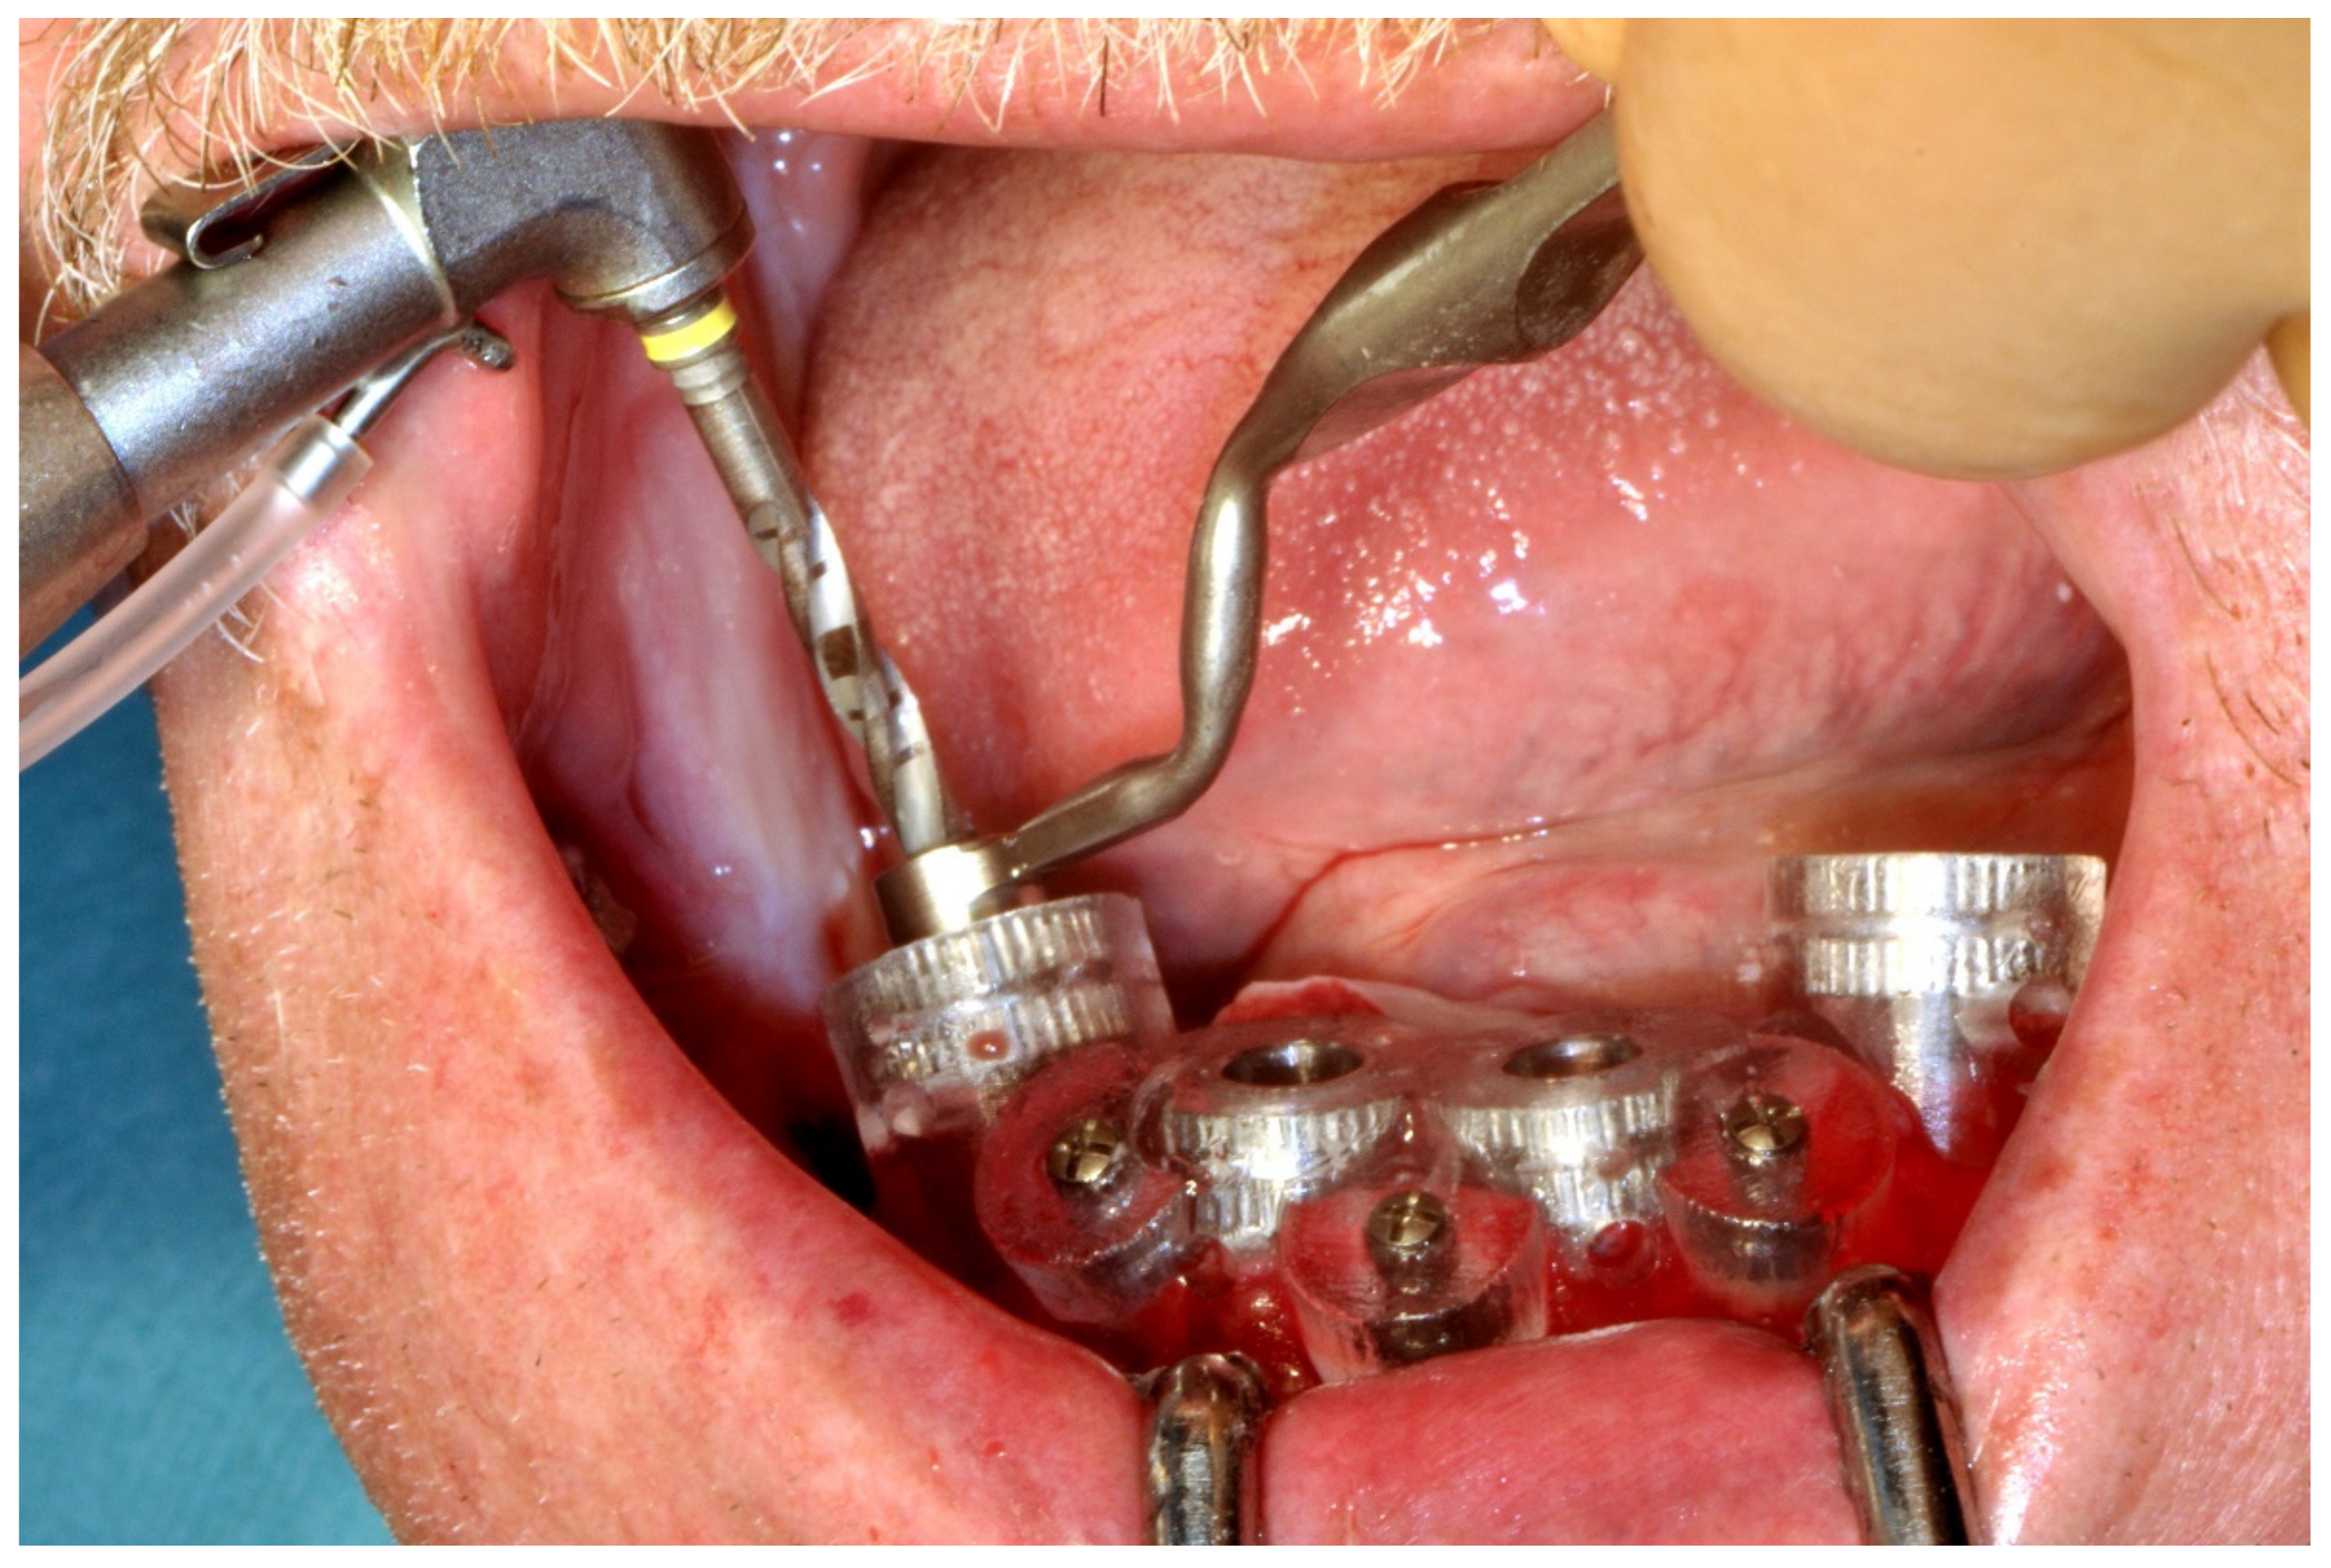

6.1.4. Intra-Operative Documentation:

In November 2017, two guided dental implants were placed at sites # 12 and # 21 (Figure 7, Figure 8, Figure 9, Figure 10 and Figure 11).

Figure 8.

Implant bed preparation by using guided drills inserted into specific ad hoc drill handles.